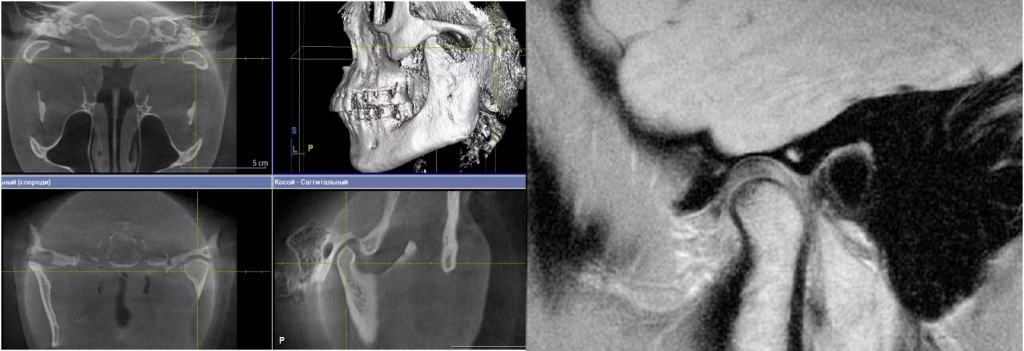

КТ ВНЧС дает объемное изображение суставных головок, суставных ямок и костных структур без искажений.

Отличие КТ ВНЧС от других методов

В отличие от ортопантомограммы и прицельных снимков, КТ дает трехмерное изображение суставных структур. Это особенно важно при оценке формы суставной головки и суставной ямки. Компьютерная томография показывает именно костные элементы сустава, что делает ее незаменимой при подозрении на дегенеративные изменения и травмы.